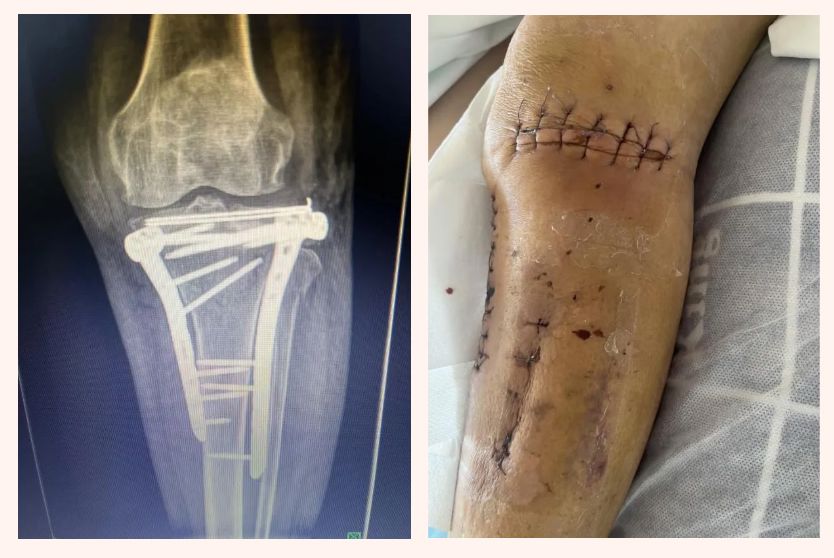

患者徐某因车祸致右胫骨平台骨折(Schatzker分型Ⅲ型),经同款微创术式治疗后,同样实现了外侧平台精准复位,且创伤小、恢复期短,临床疗效显著。